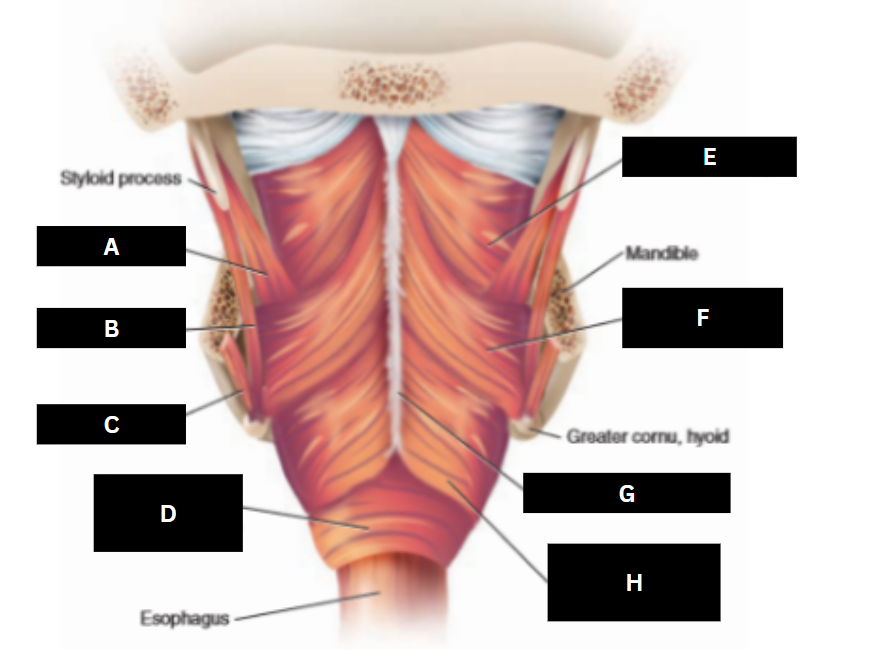

Stylopharyngeus

A

Styloglossus

B

Stylohyoid

C

Cricopharyngeus

D

Superior pharyngeal constrictor

E

Middle pharyngeal constrictor

F

Pharyngeal raphe

G

Inferior pharyngeal constrictor

H